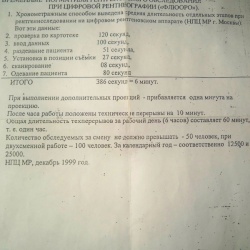

Коллеги, оказывается уже с 1999 г. существуют Временные нормативы при цифровой флюорографии. И не надо проводиь собственный хронометраж. На СПР коллега поделился. А НПЦ МР (Научно-практический...